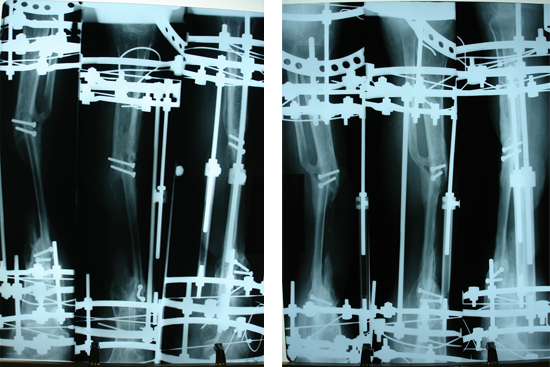

Tibialisation Of Fibula

Shankar Giri

Sudama

Wagh